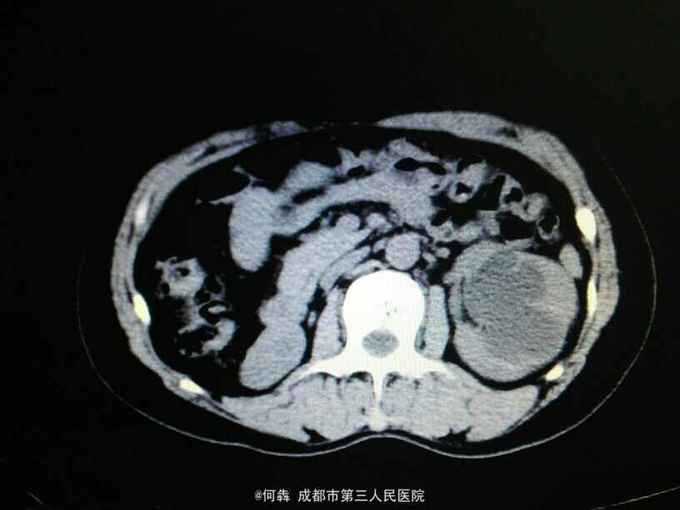

左肾区轻叩痛。尿常规:白细胞72个/ul。CT见图片。左侧GFR42.27,右侧GFR14.46。

左肾盂输尿管交界处结石 左肾重度积水,左肾结石,右肾萎缩,尿路感染。